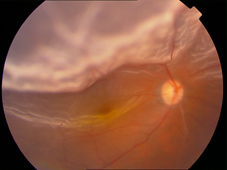

An image of Retinal Detachment

The retina is a thin sheet of light sensitive nerve tissue lining the inside of the eye which functions like the film of camera. Retinal detachment (RD) occurs when the retina separates from the back wall of the eye and is usually caused by break in the retina. RD is one of the major human eye diseases which can lead to severe visual impairment or even blindness unless it is treated surgically. Scleral buckling surgery is one of the most commonly performed operations to treat RD. In the surgery, silicone rubber explants are sewed externally on to the eye wall (sclera) overlying the retinal tear. The explants indent the sclera against the retina and close retinal tear by relieving the force tracking on the tear.